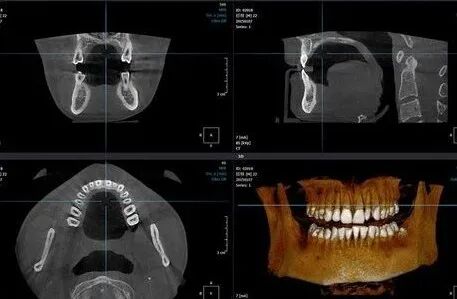

牙科CT:通过三维影像医生可以360°旋转查看口腔状况,高准判断根尖囊肿的范围、多生牙的位置、种植牙区域颌骨的高度、宽度等等信息。